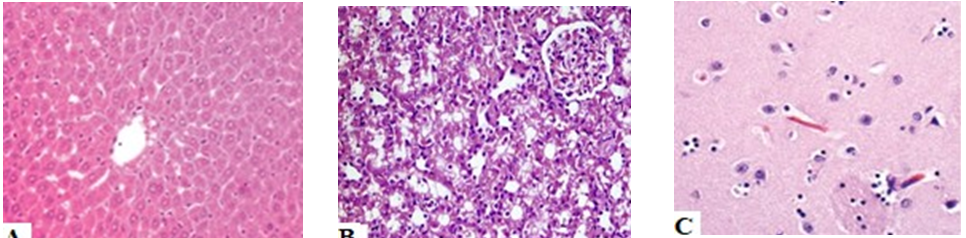

Fig. 5: Different histological specimens of experimental rats

Histopathological observation of tissues of various organs (brain, liver, and kidney) after administration of green tea extract (orally and transdermal) (fig. 5) showed no changes in the organs’ tissues and cells of rats’specimens. Confirming that short time periods and such doses of oral and/or transdermal administration of green tea extract formulations doesn’t cause any toxicity to brain, liver, nor kidney of the tested rats.

Fig. different histological specimens of experimental rats (H and E, ×400) (a) liver, (b) kidney and (c) brain, show normal tissues with non-remarkable changes with control specimens.